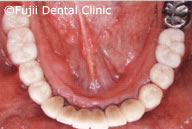

| 補綴物(クラウン)装着時口腔内写真 |

左上第二小臼歯破折による痛みがあり来院されましたが、下顎左右の大臼歯の欠損により、後方の歯が手前に傾斜、上顎大臼歯の挺出、噛み合わせのバランスが崩れてしまっていました。下顎大臼歯にインプラントを埋入することにより咬合は回復しました。挺出した上顎大臼歯は、クラウンをかぶせましたが、歯が欠損した時点ですぐ治療をしていれば、上の歯の治療は行わず最小限の治療にとどめられたでしょう。